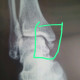

ALO Dokter, Selamat siang. Saya ingin konsultasi ttg pasien lk usia 40 tahunan, riwayat terkilir saat berolahraga 2 bulan yll. Sudah rontgen dan hasilnya seperti yg dilampirkan. Saat ini nyerinya masih hilang timbul terutama saat berjalan dgn skala nyeri 5-6. Kira2 apakah dari rontgen tampak fraktur atau nyeri diakibatkan sprain/strain dok? Terima kasih

Alo dokter, kalau dari anamnesis dan xraynya tampak fraktur malleolus medial. Mungkin bisa dikonfim dengan foto ankle lateral.

Alo dokter, sepertinya ini gambaran dari bone spur ya, bentuknya yang tidak regular seperti tulang pada umumnya. Lalu terkait kondisinya saat ini menurut saya disebabkan oleh sprain muscle/tendon. Bila gejala tidak kunjung membaik, saran saya dapat dilakukan MRI untuk menilai otot/tendon nya. Semoga dapat membantu :)

ALO Dokter Albert.. Spur seperti ini harusnya proses lama ya, dok. Nyeri saat ini apakah akibat ruptur ligament?